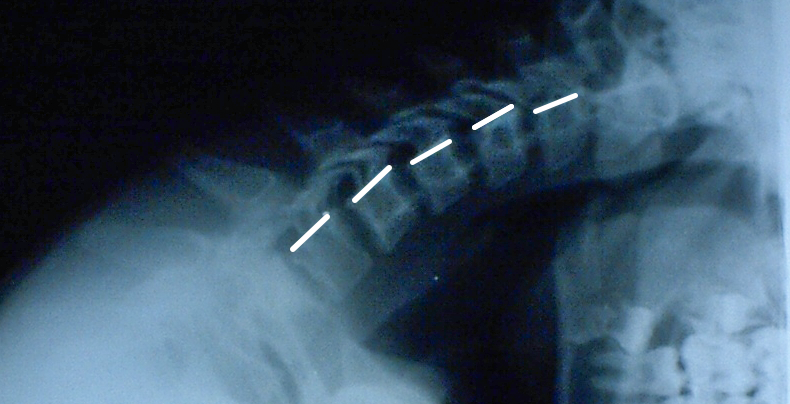

Нестабильность C4-C5: причины и диагностика